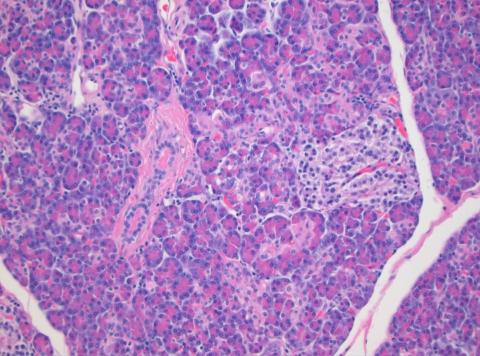

1869년 독일의 의과대학생인 랑게르한스(Paul Langerhans; 1847~1888)는 현미경으로 췌장을 관찰하다가 소화액을 만드는 세포들 사이에 점점이 흩어져 있는 세포집단을 발견했다. 마치 바다에 점점이 떠있는 섬처럼 보였다.

발견 당시 이 세포 집단들의 정체나 기능을 알 수 있는 사람은 아무도 없었다. 나중에 이 세포들이 물질대사를 조절하는 호르몬을 분비한다는 것이 알려졌고, 그제서야 발견자를 기리기 위해 점점이 떠있는 세포를 ‘랑게르한스의 (작은) 섬(islet of Langerhans)’으로 부르게 됐다.

‘랑게르한스의 작은 섬(islet of Langerhans)’은 소화액을 만드는 몽글몽글한 세포의 바다에 떠있는 느슨하게 보이는 세포집단이다. ⓒ 김대철 제공